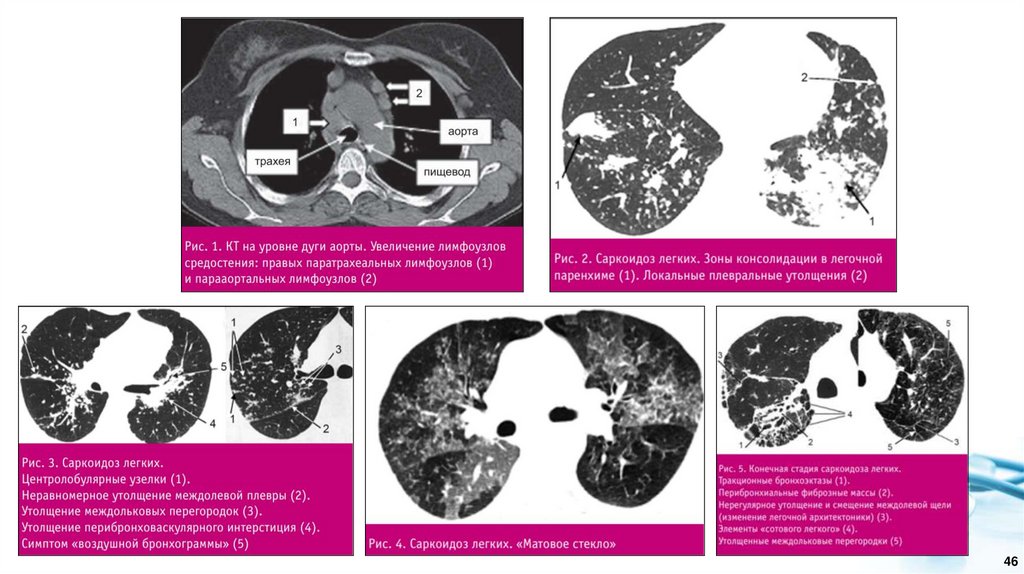

• Компьютерная томография легких. Для саркоидоза характерно увеличение лимфатических узлов

центрального отдела средостения, расположенных вдоль трахеи и главных бронхов, и корней легких.

Лимфоузлы переднего и заднего средостения обычно не вовлекаются в патологический процесс, что хорошо

видно при исследовании в боковой проекции. При КТ лимфатические узлы имеют шаровидную или

овоидную форму, однородную структуру, гладкие четкие контуры, без перифокальной инфильтрации и

склероза. При внутривенном контрастировании лимфоузлы равномерно и умеренно накапливают

контрастное вещество, что отличает эти изменения от туберкулеза. Нарушения бронхиальной проходимости

в результате сдавления бронхов лимфатическими узлами не характерно для саркоидоза. При значительном

увеличении лимфоузлов, приводящих к внешней компрессии бронхов, в легких крайне редко могут

появиться участки гиповентиляции и ателектаза. При длительном хроническом течении у трети пациентов в

структуре лимфоузлов появляются кальцинаты, которые имеют вид множественных, двусторонних,

монолитных, неправильной формы известковых включений, расположенных вдали от бронхов в центре

лимфоузлов. Характерным признаком саркоидоза легких являются диссеминации смешанного, очагового

и интерстициального характера с полиморфизмом очаговых изменений. При КТ множественные мелкие

очаги располагаются вдоль бронхососудистых пучков, междолевых щелей, костальной плевры, в

междольковых перегородках, вызывая их неравномерное («четкообразное») утолщение. Изменения

традиционно преобладают в средних отделах легких, часто в прикорневой области и сочетаются с

утолщением стенок сегментарных бронхов. Одним из редких проявлений саркоидоза при КТ могут быть

участки уплотнения легочной ткани по типу матового стекла различной протяженности и локализации.

Частота их составляет 18-83%. Морфологическим субстратом симптома «матового стекла» является

множество мельчайших очагов, неразличимых при КТ как самостоятельные образования или, в более редких

случаях, наблюдается истинное «матовое стекло» как проявление диффузного утолщения

межальвеолярных перегородок. Развитие фиброзных изменений при саркоидозе характеризуется

нарастанием ретикулярных изменений, формированием мягкотканых конгломератов с видимыми

просветами бронхов, располагающихся вокруг верхнедолевых бронхов, неотделимых от анатомических

структур корня. Отличительными признаками заключительной фиброзной стадии внутригрудного саркоидоза

являются тракционные бронхоэктазы и сотовое легкое в верхних долях легких в сочетании с нарушением

архитектоники легких.

Рис. 2. Пациентка, 49 лет. Определяется двухсторонняя диссеминация с преимущественной локализацией в

среднем легочном поясе

Рис. 1. Пациентка, 39 лет. Отмечается увеличение ВГЛУ

паратрахеальной, бифуркационной и бронхопульмональной групп

Рис. 4. Пациент, 53 года. Распространённый

пневмофиброз с элементами буллезной эмфиземы

Рис. 3. Пациентка, 62 лет. Визуализируются участки альвеолярной инфильтрации округлой формы с

неровными, лучистыми контурами (саркоидомы), расположенные перибронхиально